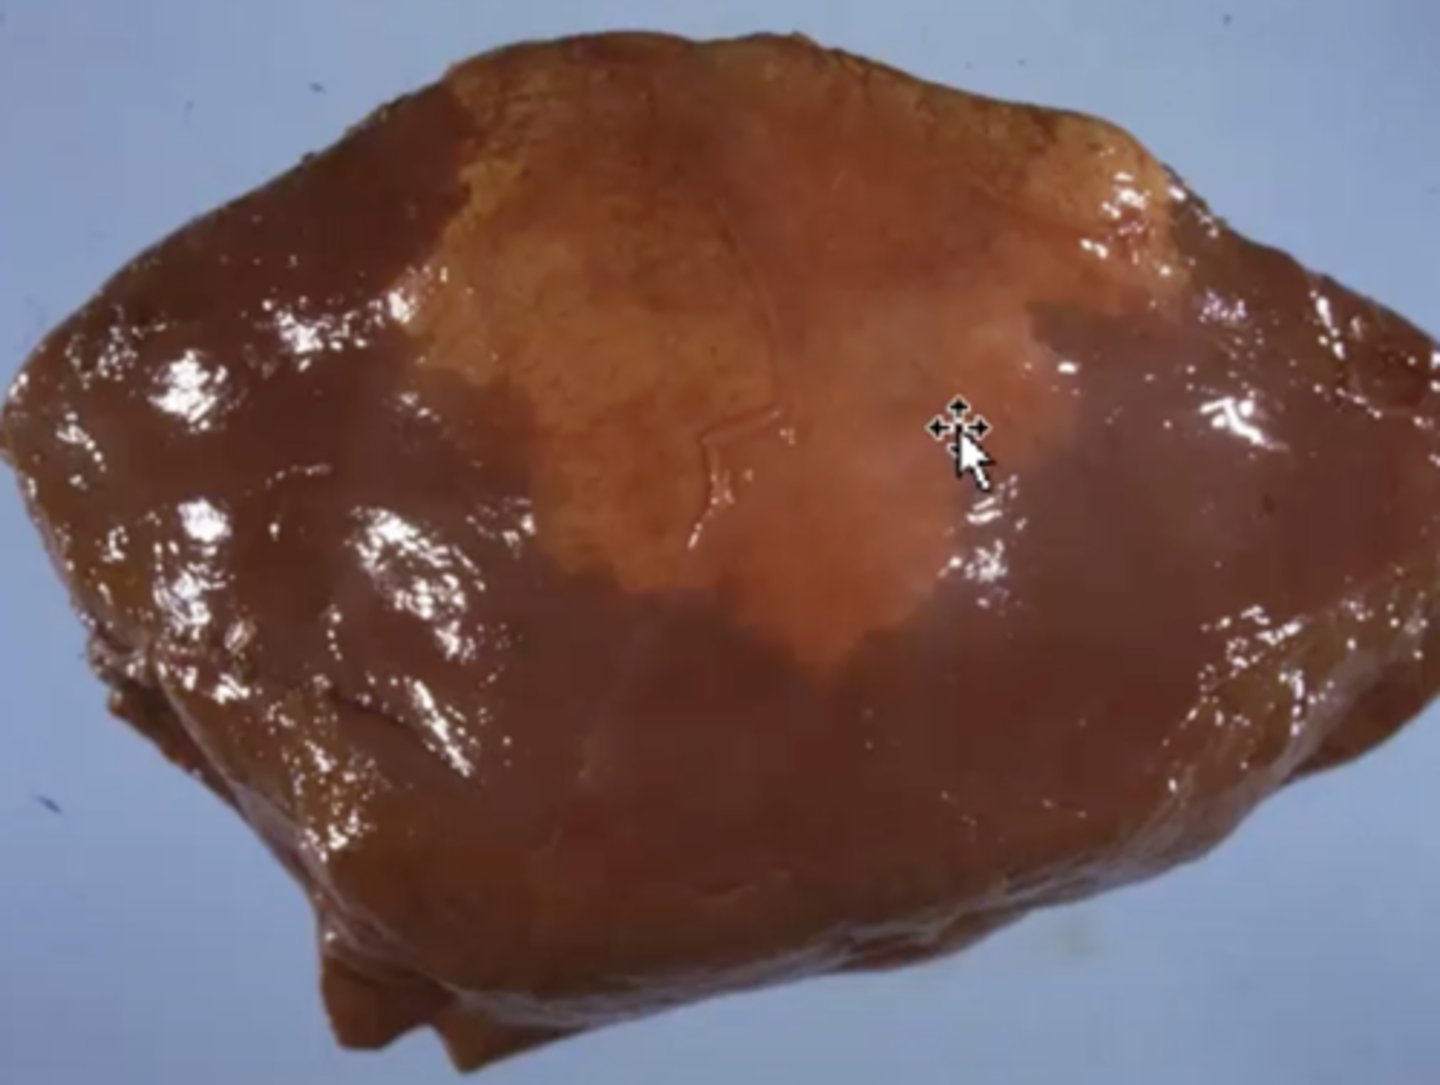

Hepatic lipidosis - glycogen caused

-very common

-notice the sinusoids are pushed out of the way in the histopath image

-can see in starvation cases + obesity

What has caused this gross and histologic lesions?

Hepatic lipidosis

Cat liver: What is wrong here?

Hyperlipemia

Pony liver: What caused this gross appearance?

Fatty liver- caused by hepatocellular steatosis (lipidosis)

Monkey liver: What caused this gross appearance?